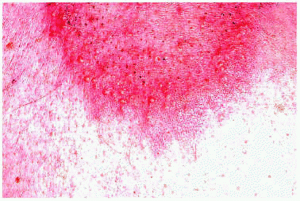

El estudio histopatológico demuestra, en la primera fase o celulítica, un edema en la dermis que está infiltrada por leucocitos, predominantemente eosinófilos, que raramente pueden extenderse a la hipodermis o al músculo. No hay signos de vasculitis. Más tarde, el infiltrado descrito se acompaña de histiocitos y aparecen las características «figuras en llama» compuestas por haces de colágeno degenerado marcadamente eosinófilo rodeadas por un infiltrado granulomatoso (fig. 7). La aparición de las «figuras en llama» se debe al depósito de la proteína básica mayor del eosinófilo en las fibras de colágeno. Aunque se pretendió que estas figuras eran patognomónicas del síndrome de Wells, se han encontrado en otras enfermedades, incluyendo las picaduras de insecto, el penfigoide ampolloso o las parasitosis, entre otras64-67. En la fase de resolución se produce una desaparición gradual de los eosinófilos, con la presencia aún de histiocitos y células gigantes alrededor de las figuras en llama formando microgranulomas62.

Fig. 7.--Celulitis eosinofílica: figuras «en llama».